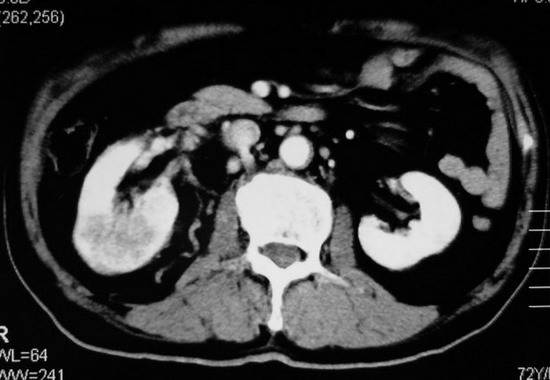

以下是引用杀毒软件在2008-11-17 19:15:00的发言:[br]考虑------右肾癌合并肾静脉---同侧肾上腺受侵可能性大

以下是引用zjzjr在2008-11-17 20:45:00的发言:[br]考虑------右肾癌合并肾静脉---同侧肾上腺受侵可能性大及腹膜后淋巴结转移.